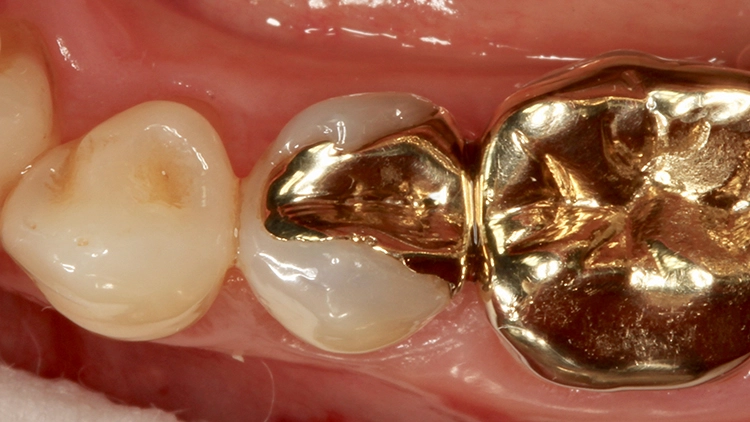

Die Abbildungen 18 und 19 zeigen dieselbe Situation nach 2 Jahren, die Abbildungen 20 und 21 nach 5 Jahren und die Abbildungen 22 und 23 nach 11 Jahren. Die direkte Kompositrestauration zeigte sich im gesamten Beobachtungszeitraum nahezu unverändert; es haben sich lediglich etwas Zahnsteinauflagerungen approximal gebildet, die im Rahmen der demnächst geplanten PZR beseitigt werden. Beim Nachkontrolltermin nach 11 Jahren wurde zudem eine erneute Röntgenaufnahme angefertigt (Abb. 24).

Gut erkennbar sind hingegen die perfekte Randdichtigkeit der Venus Diamond-Restauration an Zahn 25 und die sehr gute Röntgenopazität. Somit konnten dem inzwischen 11 Jahre alten Inlayersatz in direkter Technik mit Komposit durchweg gute Noten vergeben werden. Auch die Patientin zeigte sich mit der Versorgung nach wie vor sehr zufrieden – sie sah ihre damalige Entscheidung zu Gunsten der direkten Versorgungsvariante bestätigt.